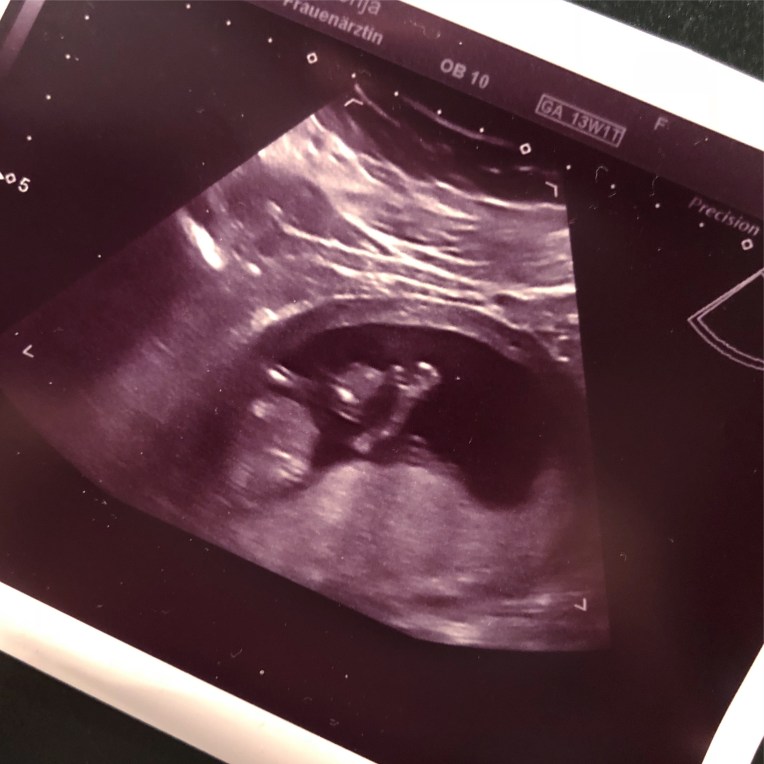

Zweites und noch viel emotionaleres Highlight der Woche: Beim letzten Ultraschall haben wir unser Kleines ca. 10mn lang gesehen, da wir uns dazu entschieden haben ein ETS zu machen und natürlich alles genau untersucht wurde. Es war so faszinierend zu sehen, wie es sich bewegt und mit den Beinen strampelt. Kurz zum Ende hat ist es eingeschlafen und war ganz ruhig. Die Ärztin hat dann kurz versucht es aufzuwecken und dabei hat es uns gewunken; seine erste (aktive) Kommunikation mit uns. Was ein schöner Moment. 🙂 Heute habe ich auch die Ergebnisse des Bluttests bekommen und insgesamt waren alle Werte unauffällig und unserem Baby geht es gut.

Hier sehr ihr unser Kleines winken sehen: